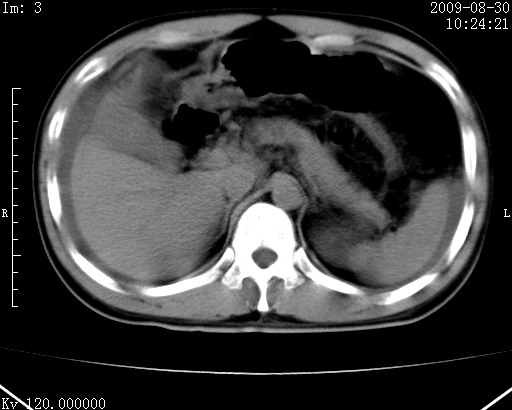

患者唐某,男31岁,已婚,本地务农。

自述入院前两天一次进食较多冷饮之后,出现阵发性上腹部疼痛,次日加剧伴恶心、呕吐,呕吐后症状稍减轻。食欲差。大便每天1-2次,量少,暗红色水样。小便赤。无畏寒、发热、咳嗽等呼吸道症状。无高血压及胃病史。

检查:体温、血压及脉搏正常.皮肤无黄染,浅表无淋巴结肿大。左腹肌紧张,左上腹有压痛,无反跳痛,可触及包块。

生化:钾、钠、氯、钙、ph正常,总胆红素和直接胆红素稍高,空腹血糖稍高。

尿淀粉酶:1256 u/l(正常60-401)。

血常规:wbc 22.4x109/l gr88% ly9.6%其余基本正常。

胃镜:急性胃炎。立位腹平片:未见异常。

下面是ct平扫,降结肠内是对比剂。

术前影像诊断:上段空肠急性缺血性坏死并腹水。建议手术治疗。

术中见上段空肠约70cm长范围坏死,从屈氏韧带远端约10cm处开始。坏死肠管肿胀变形变色,管壁明显环形增厚,部分聚成大肿块,无扭转和套叠。肠系膜上动脉分支内广泛泥沙状血栓。肠切除。

临床诊断:肠系膜上动脉梗塞并急性肠坏死。

开始时我们科也有人认为是套叠,最后统一意见,不考虑肠套。我们看到的“靶征”,“晕圈征”,“双圈征”实际上只是单根肠管的横断面。坏死肿胀后肠壁各层的密度不一样。

左侧腹小肠腔管壁明显增厚,部分内示靶征,走行异常,部分肠系膜绳样改变,肝包膜下及肠间较多液体密度,然梗阻近端肠腔积气不明显。

考虑;肠扭曲伴肠坏死。

腹部肠管肠管弥漫性增厚、肿胀,考虑为肠管缺血或淤血改变,未排除空肠管坏死。腹水。

有结果了,回顾分析,套叠只会在局部出现同心圆征,不会很长一段肠管都有,还是水肿坏死。